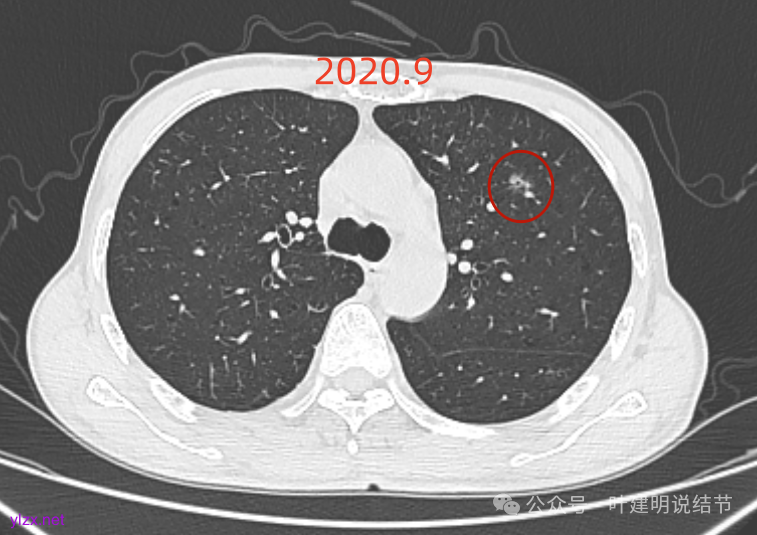

先看2020年9月的片子:

左上叶前胸壁胸膜下有小结节,磨玻璃密度,有微小血管进入,轮廓与边界清。

左上叶混合密度结节,有毛刺与空泡征,瘤肺边界稍糊,灶内密度较为杂乱不均。